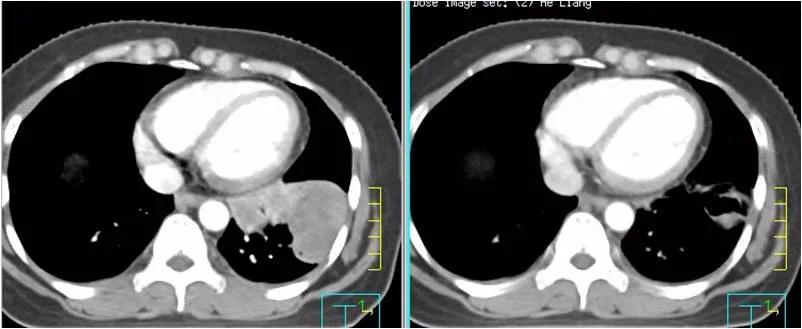

疗效评价:纵膈淋巴结及肺部转移灶均明显缩小,疗效达PR。血肿瘤指标SCC由218ng/ml下降到2.99 ng/ml。患者咳嗽、胸闷症状明显缓解。

左图为:2020-09-02治疗前 ,右图为2020-10-14两周期治疗后